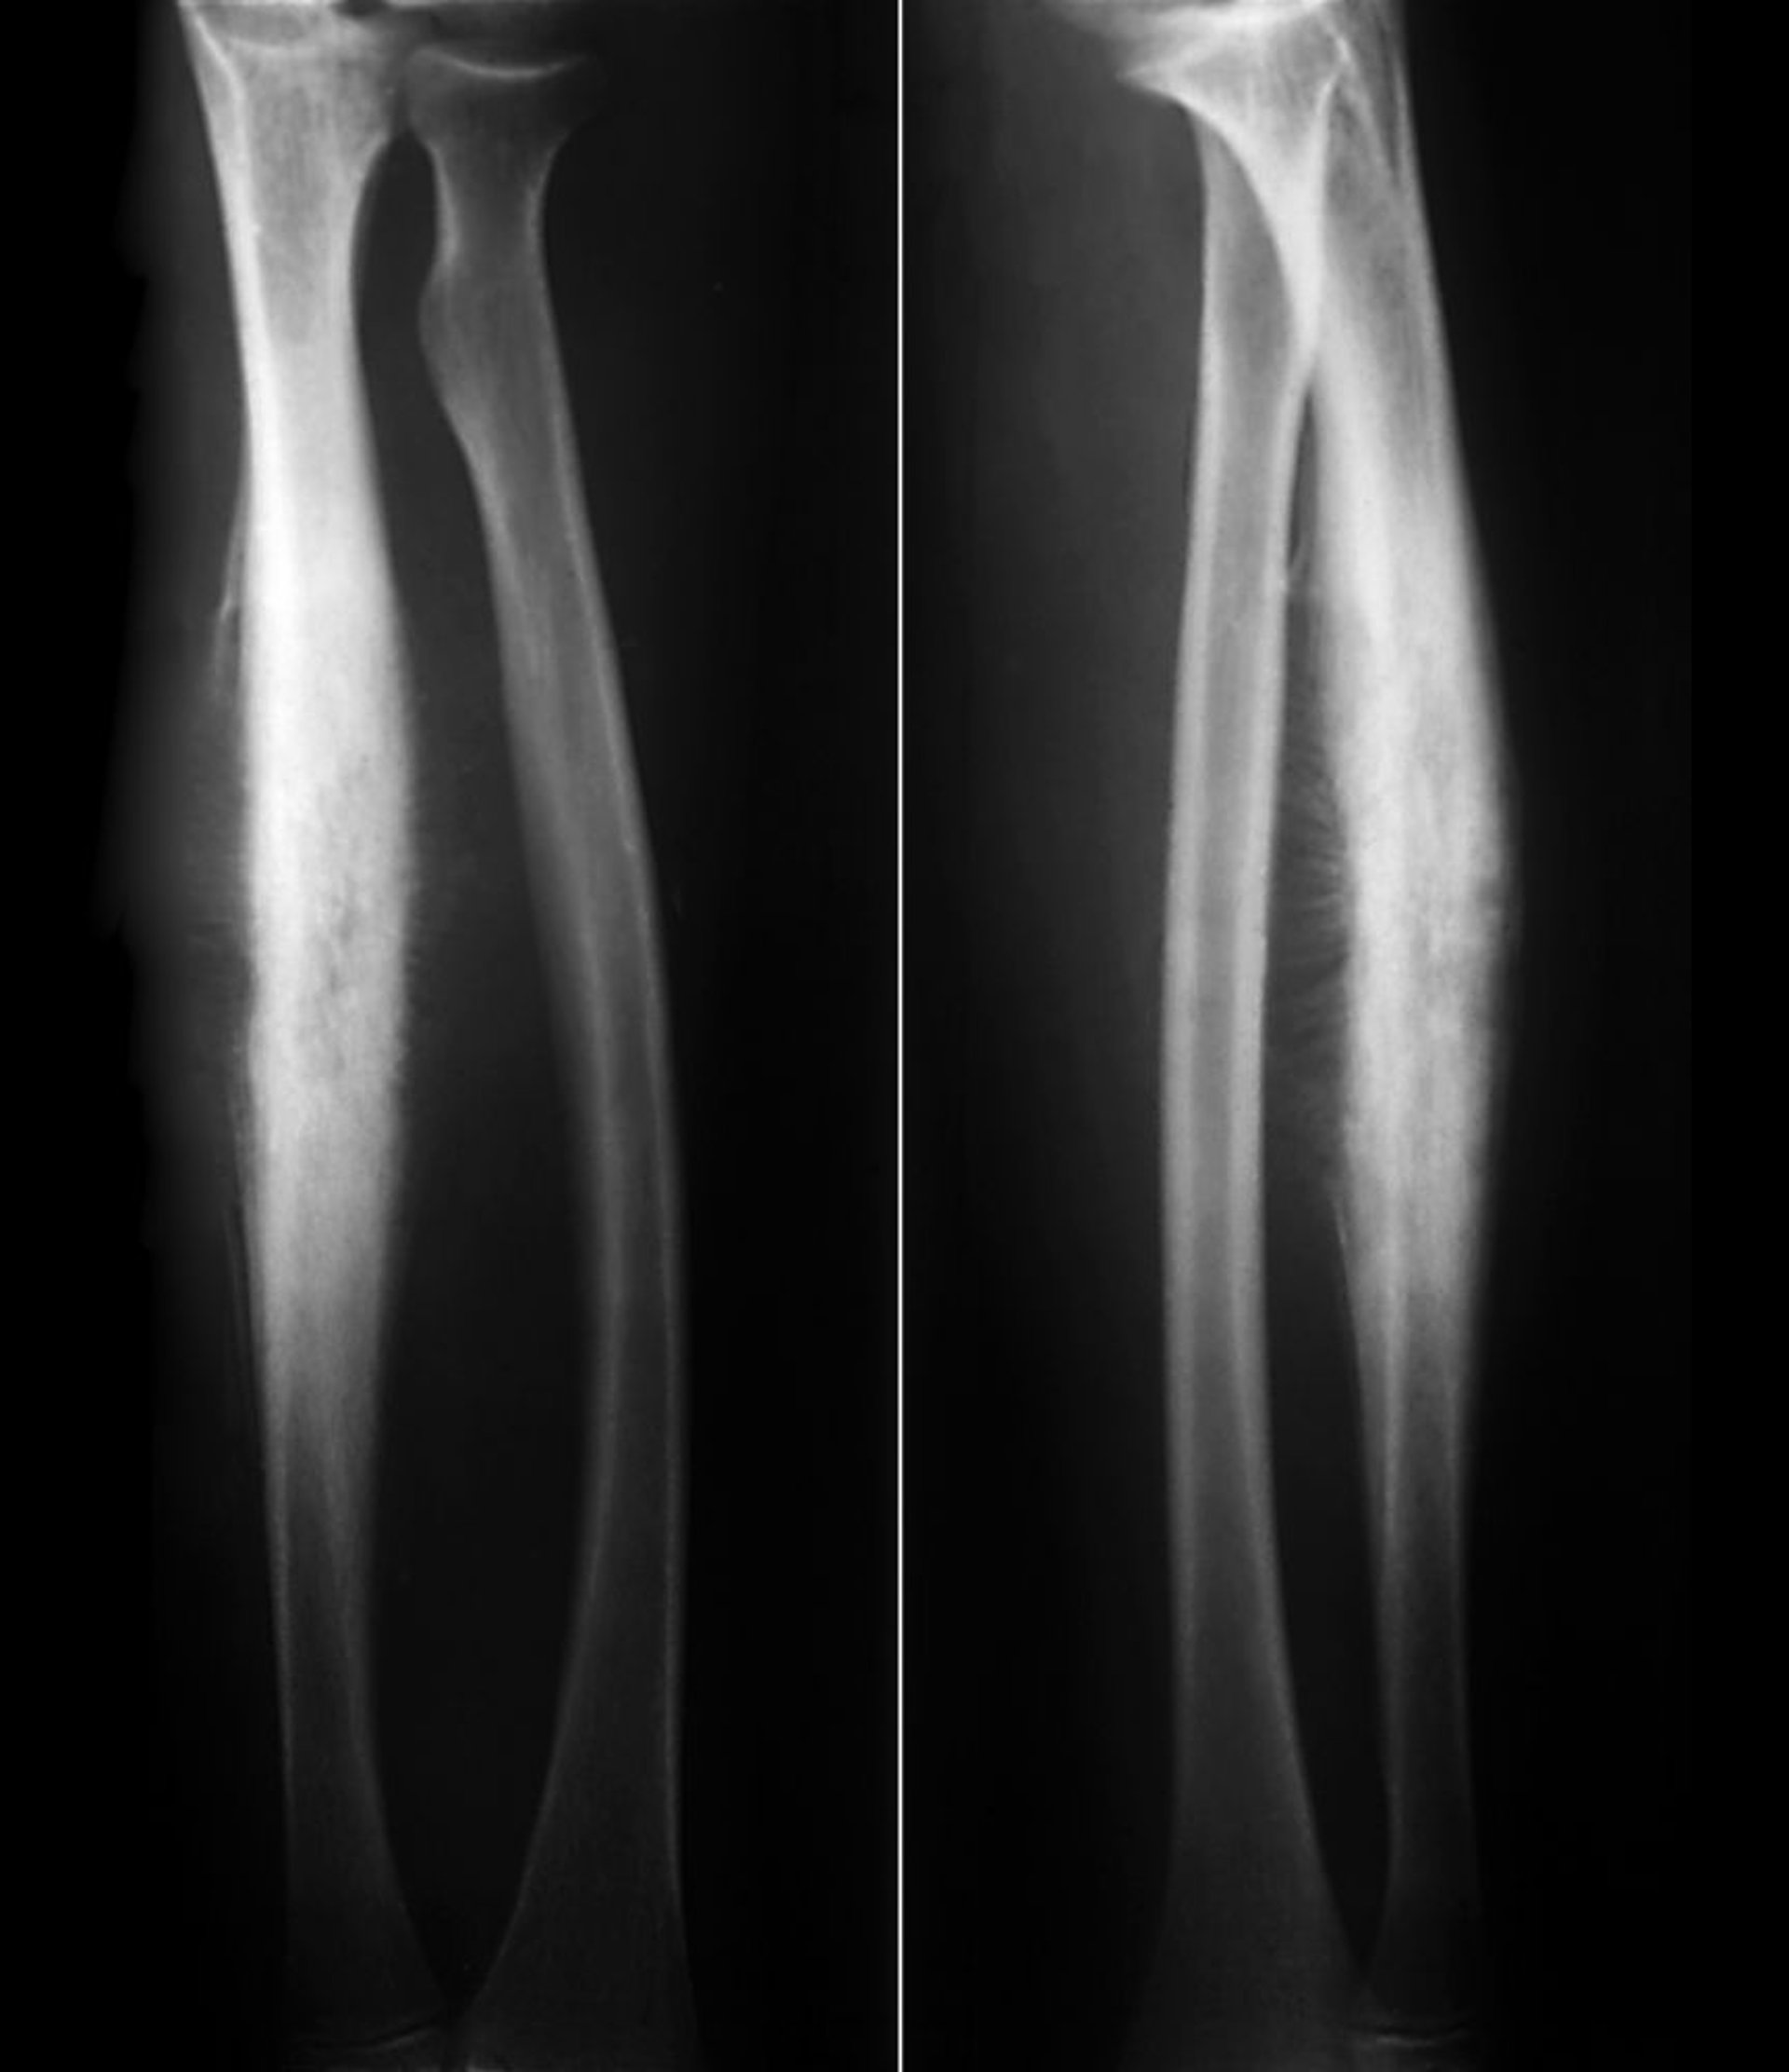

Sarcoma Ewing của xương quay

Sarcoma Ewing ở trục xương quay này cho thấy hình thành xương mới phản ứng dưới màng xương trong phản ứng màng xương dạng "ánh nắng mặt trời" điển hình cùng với phá hủy vỏ xương.